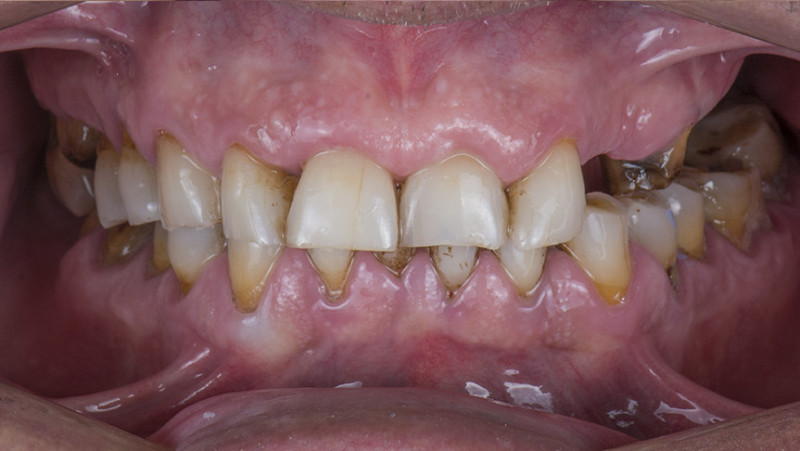

Установка керамической коронки

Изготовили и установили 22 керамические коронки EMAX и 6 виниров на нижнюю челюсть. Провели пластику десны в области 22 зуба. Устранили сильную рецессию десны в области имплантата, установленного в другой клинике.